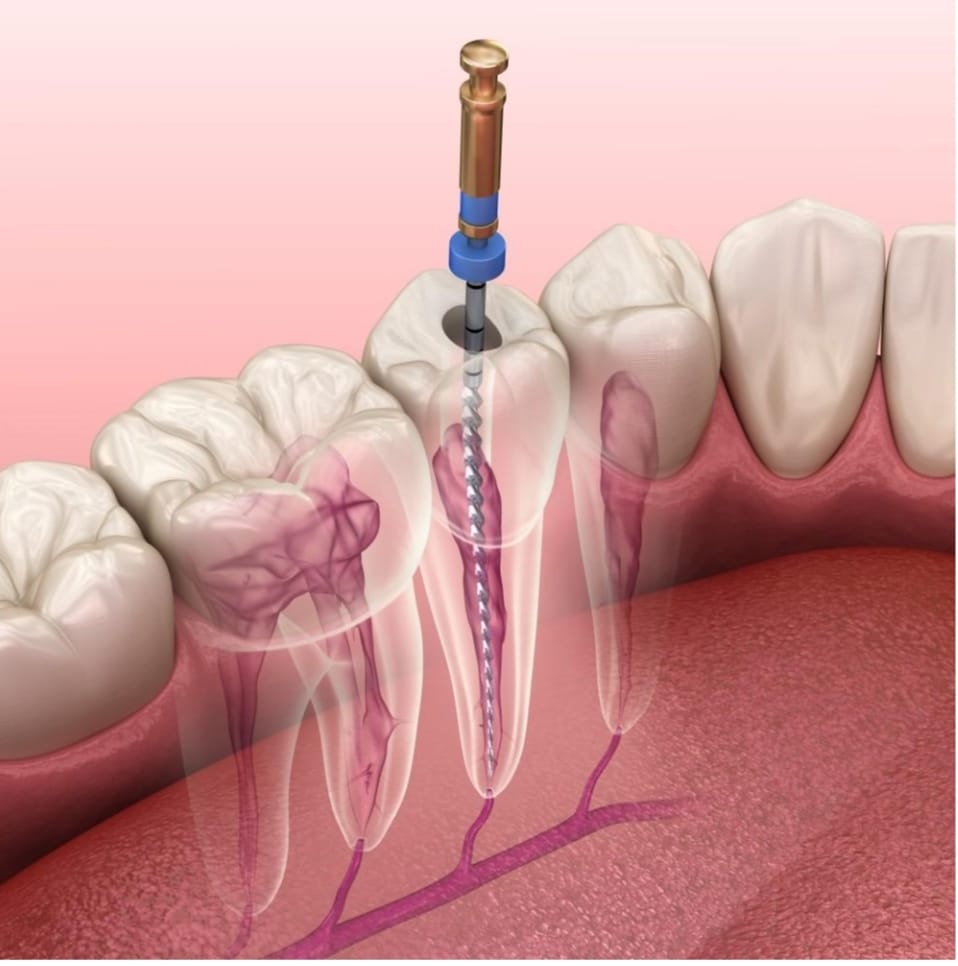

Root Canal Treatment

Root canal therapy is a pain-relieving treatment for infected teeth, removing damaged tissue and preserving the natural tooth structure. Our skilled dentists perform efficient and gentle root canals to restore oral health.